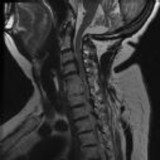

Figures 1 and 2 show sagittal and axial MRI from an 83-year-old woman with an ataxic gait, loss of dexterity, and intermittent loss of bowel and bladder control. The symptoms have been getting progressively worse over the past several weeks.

What disease process is most likely the cause of the patient’s symptoms?

4. Pigmented villonodular synovitis Discussion: B

The patient has a pannus at the C1-2 articulation that is compressing the spinal cord and causing myelopathy symptoms. The development of a pannus at this location has been associated with rheumatoid arthritis. Steinberger and associates showed increased morbidity and mortality when using an anterior approach and the surgery took longer than 4 hours. Chieng and associates showed better outcomes and lower complications rates using a posterior approach.